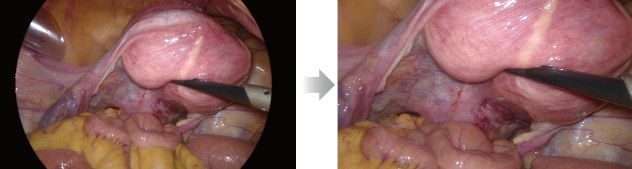

Laparoscope scene

Intelligent Image Algorithm, Even in Extreme Circumstances

Intelligent Image Algorithm, Even in Extreme Circumstances

A variety of image post-processing algorithms make up for uneven lighting, local overexposure, thick fog etc., delivering clear, structured and layered images even in extreme scenarios.

Homogenous Brightness

Detail Enhancement

Color Enhancement

Before

After

Laparoscope - One Touch to Full Screen